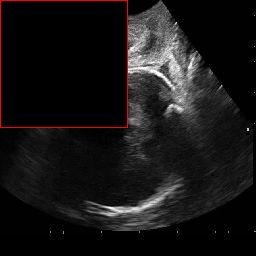

Figure 4 and Figure 7 provide visual comparisons of segmentation masks generated by DAUNet and other competing methods on representative samples from both datasets. As illustrated in Figure 4, DAUNet produces more accurate and smoother boundary delineations, closely aligning with the ground truth annotations, even in challenging low-contrast regions or under partial occlusion. A similar performance can be observed in Figure 7, where proposed model accurately identify the pulmonary embolism regions. It is worth nothing that the proposed model achieve best performance in two different imaging modalities, consisting of different sized regions of interest and number of classes demonstrating a good generalization.